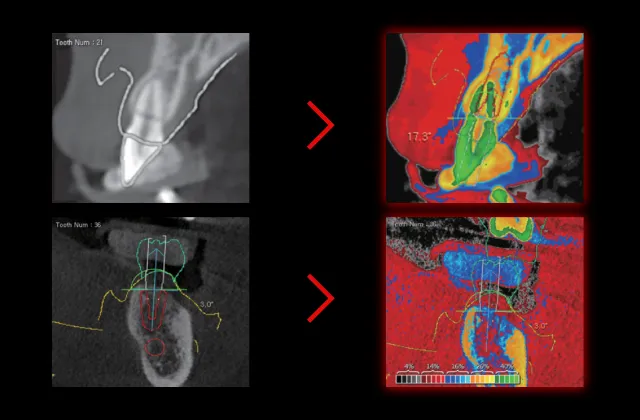

Digital Eye

Color-Coded Analysis of bone morphology & density

While CBCT has 256 grayscale tones, our eyes can only see 16 shades. Windowing converts these grayscale variations into vivid, uniformly calibrated colors, known as the Digital EYE. This aids in bone health assessment, precise implant procedures, and predicting initial stability for immediate loading.